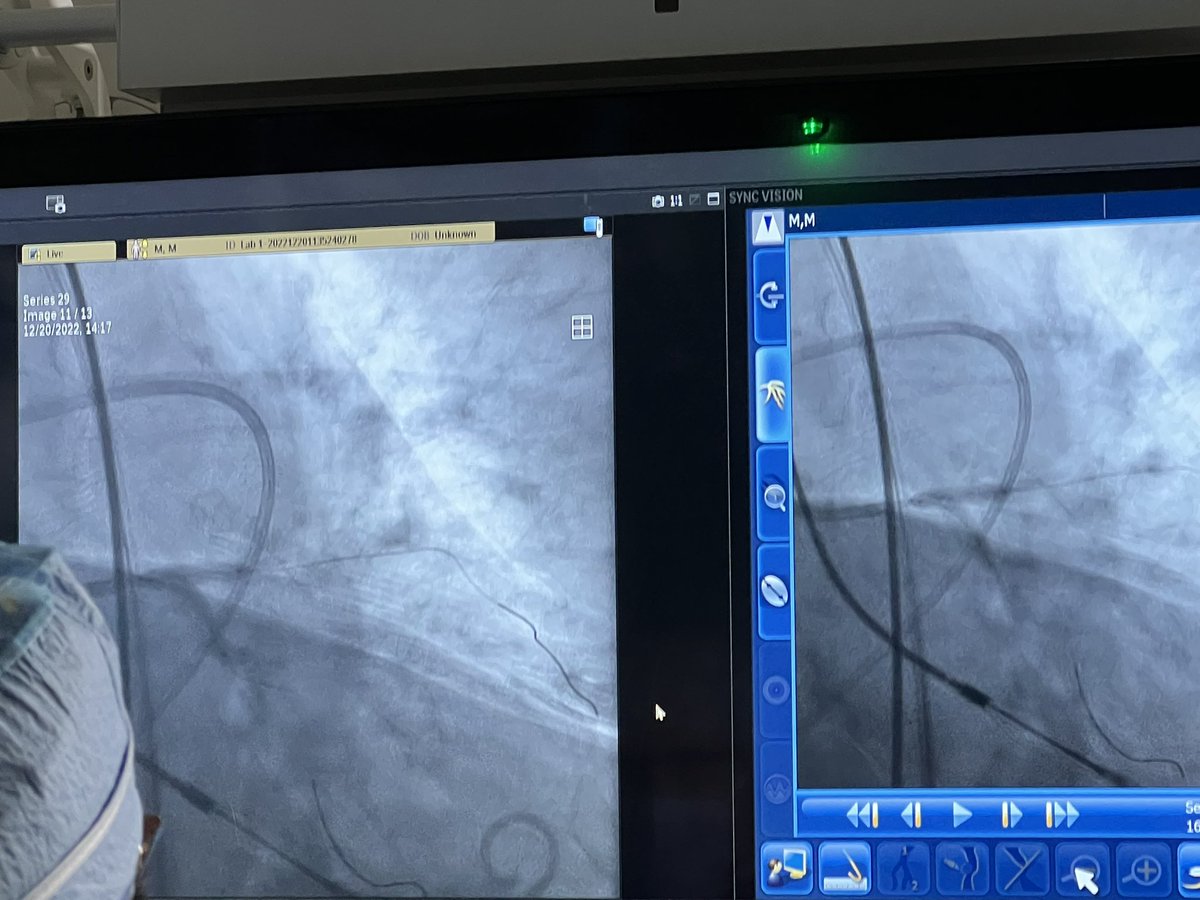

Excited to be part of the future of transvalvular ventricular #unloading with the #Impella #ECP from @Abiomed First and only center in New England to offer this 9Fr #innovation for complex #PCI to our patients and IC/HF Fellows @TuftsMedicalCtr Single Angioseal on the way out!

FIRST CASES OF THE ABIOMED PIVOTAL IMPELLA ECP STUDY.... @Ascensionorg St. John in Detroit, with @DrAmirKaki Fantastic ECP device performance: easy AoV crossing, LV position optimized, high pump flows & excellent hemodynamic support during 2 unprotected left main Protected PCI